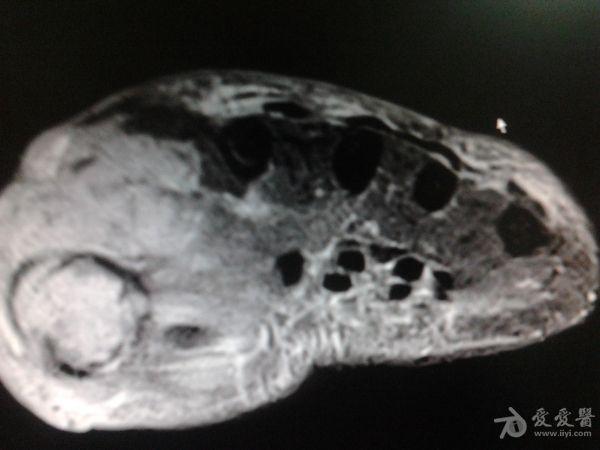

右第一掌骨、大多角骨肿瘤

男性患者,81岁,右手肿痛3个多月。无任何其它症状。体查:右手第一掌骨部肿胀明显,第一指活动受限,余四指活动可,腕关节活动小部分受限,活动时会痛。影像学检查如下。活检示:弥漫性大B细胞淋巴瘤。大家看看需不需要截肢?现在有人主张手术;有人主张不手术,直接化疗。大家有什么看法?